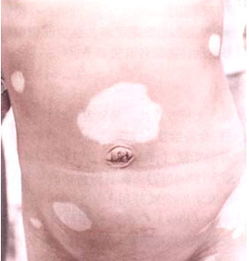

晚期白癜风的危害?白癜风是一常见的多发性色素皮肤性疾病,常见于青年妇女,在其他各个年龄段也有发生 ,主要是由于肤的黑素细胞功能消失引起的,随着社会和经济的发展,白癜风这种疾病受到了更多人的关注,对于这种疾病患上之后对于健康有影响,对于美观、对于社交都会造成一定的影响,我们了解一下晚期白癜风的危害。